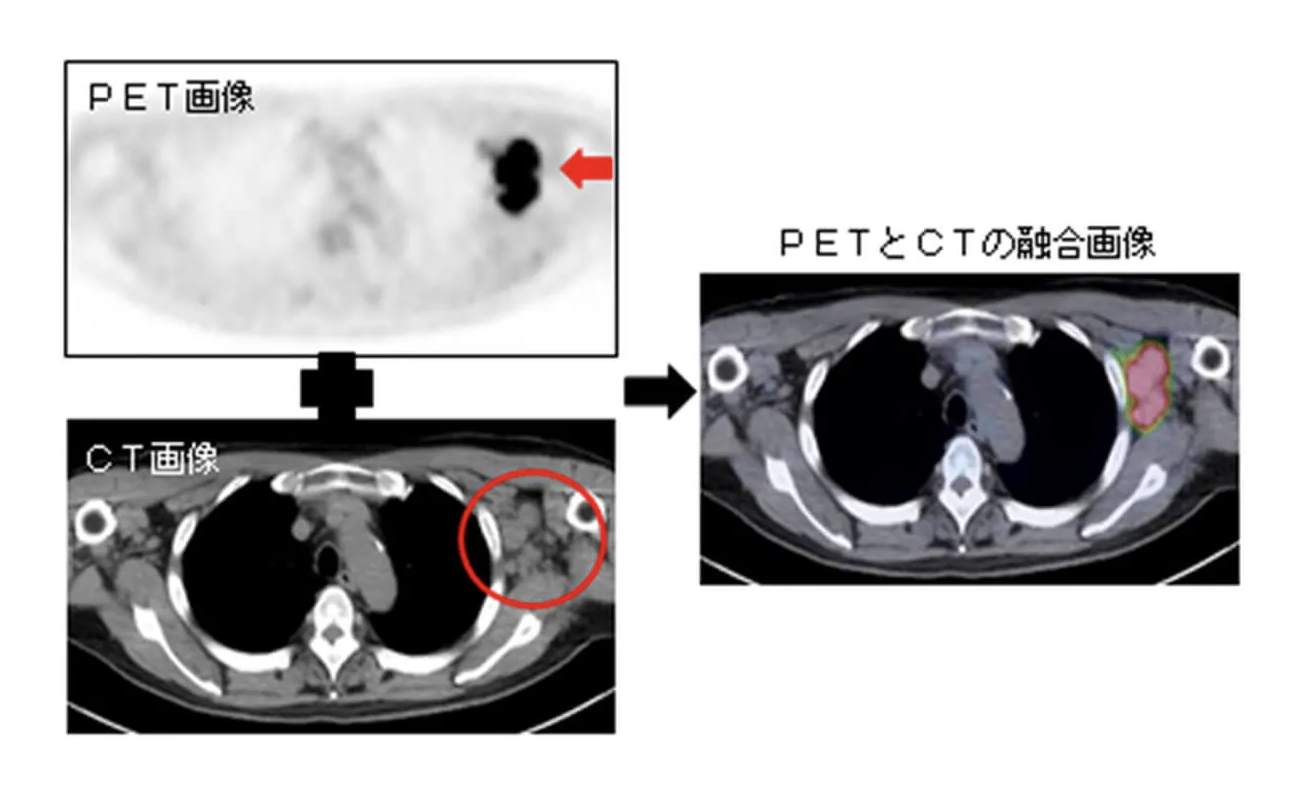

その後有給を取ってPETCTのため某病院へ。新しく綺麗な建物です。放射線科のドクターの問診を受けてから別の階へ。PETCTはもう皆様ご存知かと思いますが、湘南鎌倉病院様のHPによると、

『PETとは、

(ポジトロン・エミッション・トモグラフィー、陽電子放射断層撮影)

の略称です。

ポジトロン(陽電子)という放射線を出す物質を含んだ薬を注射し、そこから出る放射線を検出することにより、薬の体内分布を画像化します。多くの場合、18F-FDG(以下、FDG)という薬を用い、がんを診断します。

FDGとは、正確には fluorodeoxyglucose (フルオロデオキシグルコース)といい、ブドウ糖(グルコース)によく似た薬剤です。

PET検査ではFDGの集まり具合でがんの存在、がんがあるのかないのかを調べます。

しかし、PET検査のみではFDGが集まった部分を判定することが難しく、別に撮影されたCTやMRIとの比較を必要としていました。

そこで開発されたのがPETとCTの一体型装置であるPET/CTです。

CT検査では身体の外からX線を当て、身体を通りぬけたX線を測定して、いろいろな臓器の形をうつしだします。

PET/CT装置はPETとCTをひとつにまとめた装置で、PETでがんの存在を判定し、CTでがんのある臓器を探し当てます。PET検査とCT検査を同時におこなうことになりますので、FDGが集まった部分とCTとの比較が簡単になり、がんの存在する部位を正確に診断することができます。』

まあ、わたしの場合はK部長が指摘された、縦隔リンパ節に行っているかどうか(ステージが変わるから)、あとは他に遠隔転移がないかどうかのチェック目的だったものと思われます。その後また50分くらいしてCT撮像のため呼ばれました。被曝しまくりんぐだよ!!!

2回撮影する理由は、診断の精度を増すことと、悪性腫瘍は正常の脳組織同様のブドウ糖大好き、大喰らいな性質を持ち、時間が経っても尚貪欲に食べ続けるので2回目撮影時の集積の方が濃くなっている傾向にあり、この性質も良悪性の鑑別に使えるから。らしいです。

その指標と言いますか、単位が(Standardized Uptake Value maximum:標準化最大集積値)

です。

SUVmax値は、病巣における放射能濃度を注射されたFDGの総量と体重で補正した数値で表されます。具体的には、以下の計算式で求められます。

SUVmax = 病巣の放射能濃度(kBq/mL) × 体重(kg) / 投与放射能量(kBq)

この値が高いほど、その部位でのブドウ糖代謝が活発であることを示します。一般的に、悪性腫瘍では高い値を示すことが多く、良性病変では比較的低い値にとどまる傾向があります。2.5が良悪性のカットオフだそうですが、もちろん偽陽性、偽陰性はあり得ます。わたしは前日にこの論文を読んだので↓